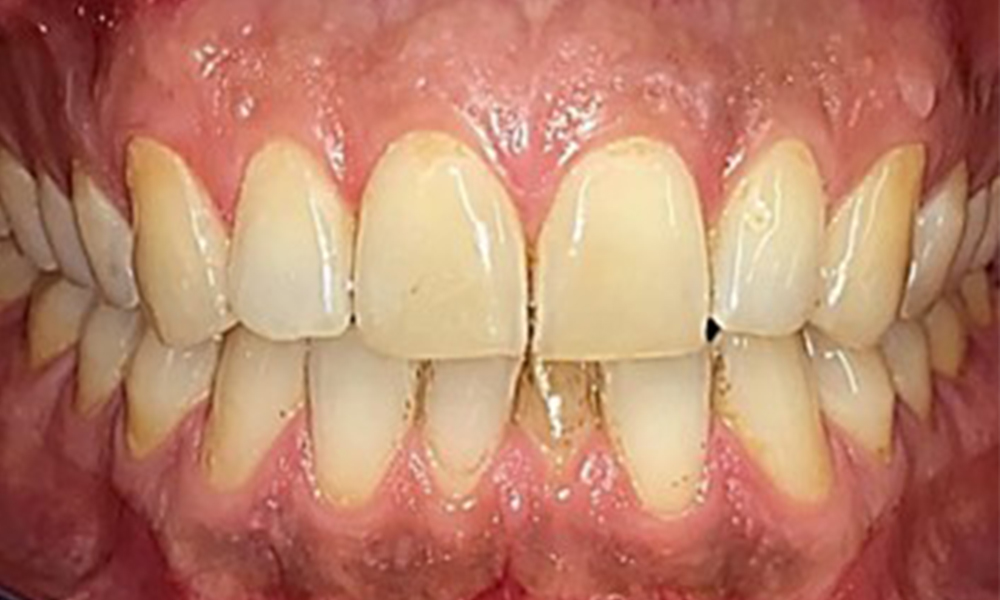

Extraoral and intraoral findings

There were no pathological extraoral findings. During intraoral examination, inspection of the frontal view revealed brownish discolouration near the keratinised gingiva and at the transition to the moveable mucosa (Fig. 2), which could be attributed to nicotine consumption. Whitish mucosal lesions were observed on the palate, particularly near the maxillary molar palatal surfaces, indicating increased keratinisation and can also be attributed to nicotine consumption. The tongue was covered with a removable white and brownish coating.

Frontal view

Fig. 2 Frontal view, © Dr R. Krapf